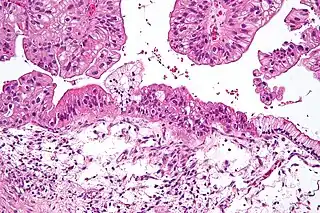

![]() Tumor mucinoso de ovario visto bajo el microscopio, tinición HE. | ||